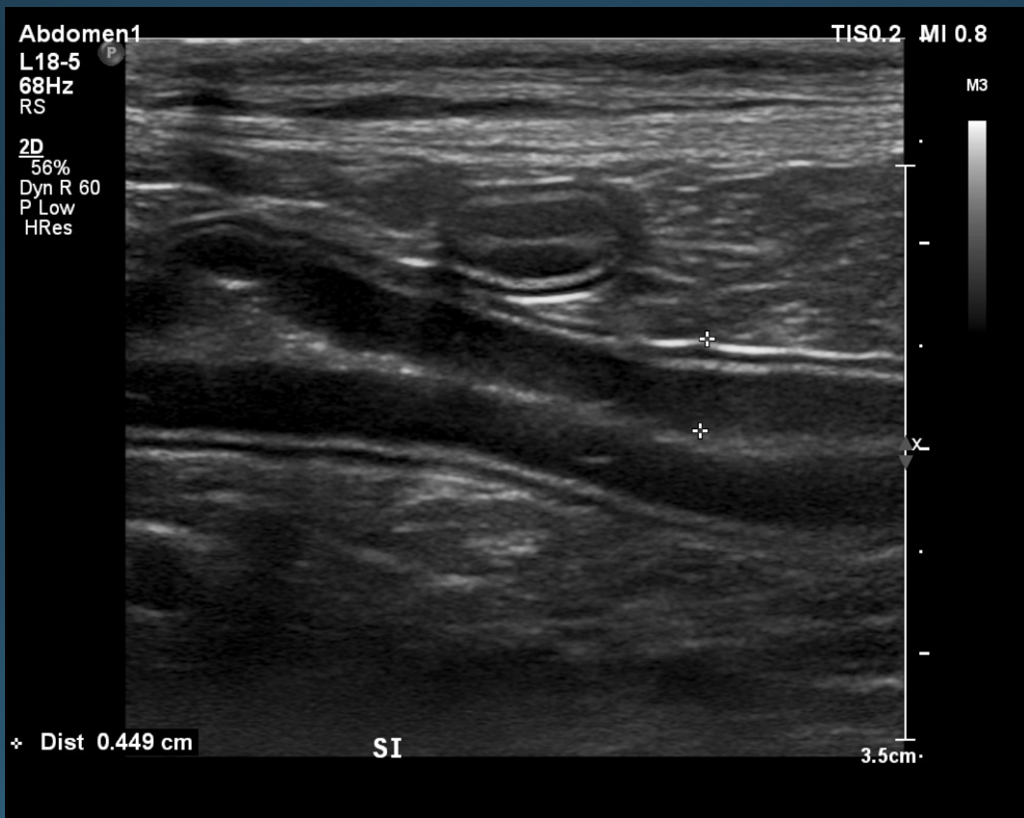

What is shown in these images?

A

normal stomach

-presence of rugal folds

-ability to assess gastric wall